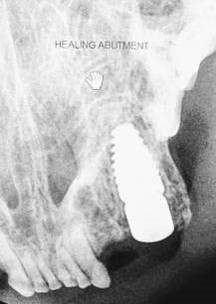

A cover screw was inserted into the implant to prevent graft material from entering the implants connect at the platform. A condenser was utilized to pack an allograft (Veterinary Transplant Service (VTS), Kent, WA) into the gap between the implant and socket walls at the crest. The graft material not only fills the “jump gap” between the implant and bone but occupies the tissue zone to the height of the free gingival margin (FGM). The graft material is incorporated into the tissue zone, acting as a scaffold to support the ridge contour profile and peri-implant tissue [15] (Figure 6). The cover screw is carefully removed, so as not to disturb the graft and replaced with a 4/5mm flat healing abutment (OCO Biomedical) with a height slightly taller than the thickness of the soft tissue so that a single stage approach. This acts as a prosthetic seal and is tightened with finger pressure utlizing a hand held hex driver. (Figure 7). The flap margins were reapproximated around the healing abutment and fixated with Securocryl, a 5/0 synthetic suture material (Securos Surgical, Fiskdale, MA) in an interrupted manner (Figure 8). Post-Op radiographs were taken to evaluate the implant/abutment interface and graft placement (Figure 9). Recovery was uneventful and the patient was discharged with post-surgical instructions to the animals owner on the same day as surgery. Cefovecin Sodium was administered SQ at a dose of 0.045 ml/lb (Zoetis,Inc., Kalamazoo, MI) and Buprenorphine (MWI Veterinary Supply, Boise, ID) at a dose of 0.01mg/kg orally every 12 hours for five days.

Figure 7: A healing abutment is placed in to the implant prior to flap closure with a height equal to the soft tissue thickness to achieve a single stage surgical approach.

Figure 9: Radiograph at immediate placement (left) and following healing abutment placement with graft placement (right) at the surgical appointment.